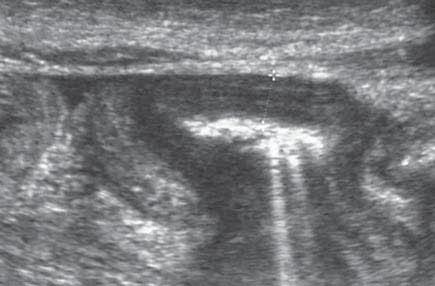

Rycina 76.15.

Rycina 76.16.

spod pachy

otoczki piersi

BABA